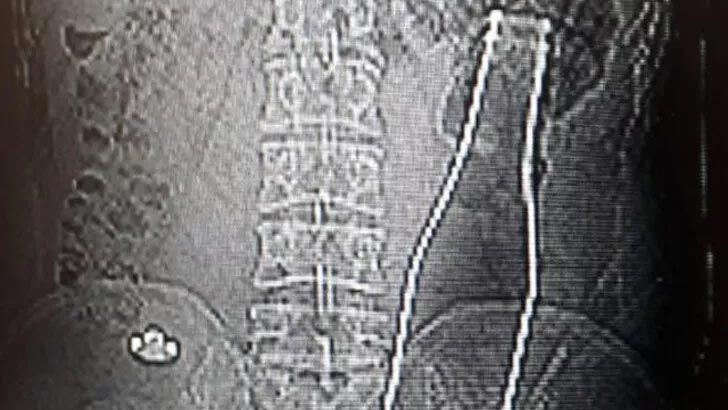

Dün akşam saatlerinde Karaman Eğitim ve Araştırma Hastanesi’ne gelen A.E., doktorlara karın ağrısı şikayetinin olduğunu söyledi. Çekilen röntgen filminde A.E.’nin kalın bağırsağının bulunduğu bölgede şişe olduğu tespit edildi.

A.E.’nin makatından sokulduğu belirlenen soda şişesi, yaklaşık 1 saat süren ameliyatla çıkarıldı.